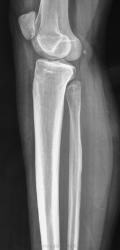

Девочка 17 лет. Беспокоят боли в в/3 голени несколько месяцев, преимущественно днём, Ночных болей нет. Клинически - некоторая болезненность при пальпации в/з правой голени по латеральной стороне. Консультировалась в частном порядке в одном из институтов радиологии. Рентгенолог по данным снимкам поставил диагноз - саркома (!) малоберцовой кости. Направлена для лечения к нам в больницу. Представлены рентгенограммы с динамикой процесса 1 месяц.

Мы убедительных данных за злокачественное образование не видим. Хотелось бы узнать мнение уважаемых коллег.

Я думаю, здесь больше данных за воспалительный процесс. У нас за последнее время тоже прошло несколько подростков с подобными изменениями, правда, в большеберцовых костях. У всех гистологически был остеомиелит.

Не вижу данных за саркому.

в целом, согласна с коллегами - не саркома, есть участок гиперостоза, в диф. ряд следует включить остеомиелит и и остеому. Но в первую очередь дообследуйте на предмет остеоид-остеомы: сделайте КТ, проведите аспириновый тест (последний, правда, работает не 100%). Возможно меня и глючит, но мое мнение, что желтой стрелкой помечено "гнездо"

На мой взгляд, вероятность остеоид-остеомы мала, все же гнездо должно быть более округлым, а здесь больше линейное просветление. У нас таких было много, сейчас вспомнила, и в малоберцовке тоже было,  пытались томографировать, когда КТ еще не было.

Ольга, я не линейное просветление имела в виду, а кнаружи от него очень мелкое уплотнение с ободком просветления по периферии. Без КТ его вряд ли удастся вывести, но теперь не узнаем...